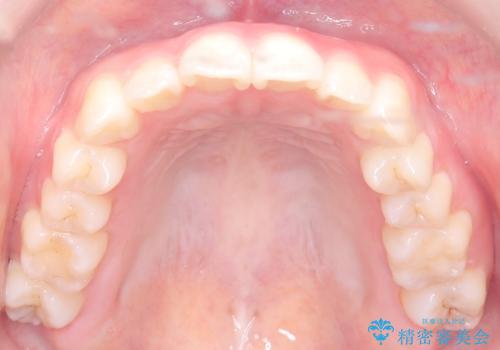

八重歯と前歯の逆の咬み合わせを、目立たない矯正で同時に改善

- 八重歯と、右上前歯(2番)が下の歯より内側に入っている反対咬合を気にされてご来院されました。精密な検査の結果、八重歯と反対咬合を同時に改善するためには、歯列全体にスペースを確保する必要があると判明。患者様のご希望から、透明で目立たないインビザライン(マウスピース矯正)による治療計画を立案しました。奥歯全体を奥へ動かす遠心移動でスペースを作り、これらの複雑な問題を一括で解消することを目指します。

今回の矯正治療では、透明なマウスピース型の装置インビザラインを使用しました。治療は、緻密なデジタル計画に基づき、奥歯から順に歯列全体を後方へ移動させる遠心移動を実施。これにより、八重歯を正しい位置に並べるためのスペースを確保しました。同時に、右上の2番を前方に誘導することで反対咬合を解消。結果として、抜歯することなく八重歯と反対咬合という複数の問題が改善され、機能的で美しい歯並びを獲得していただけました。